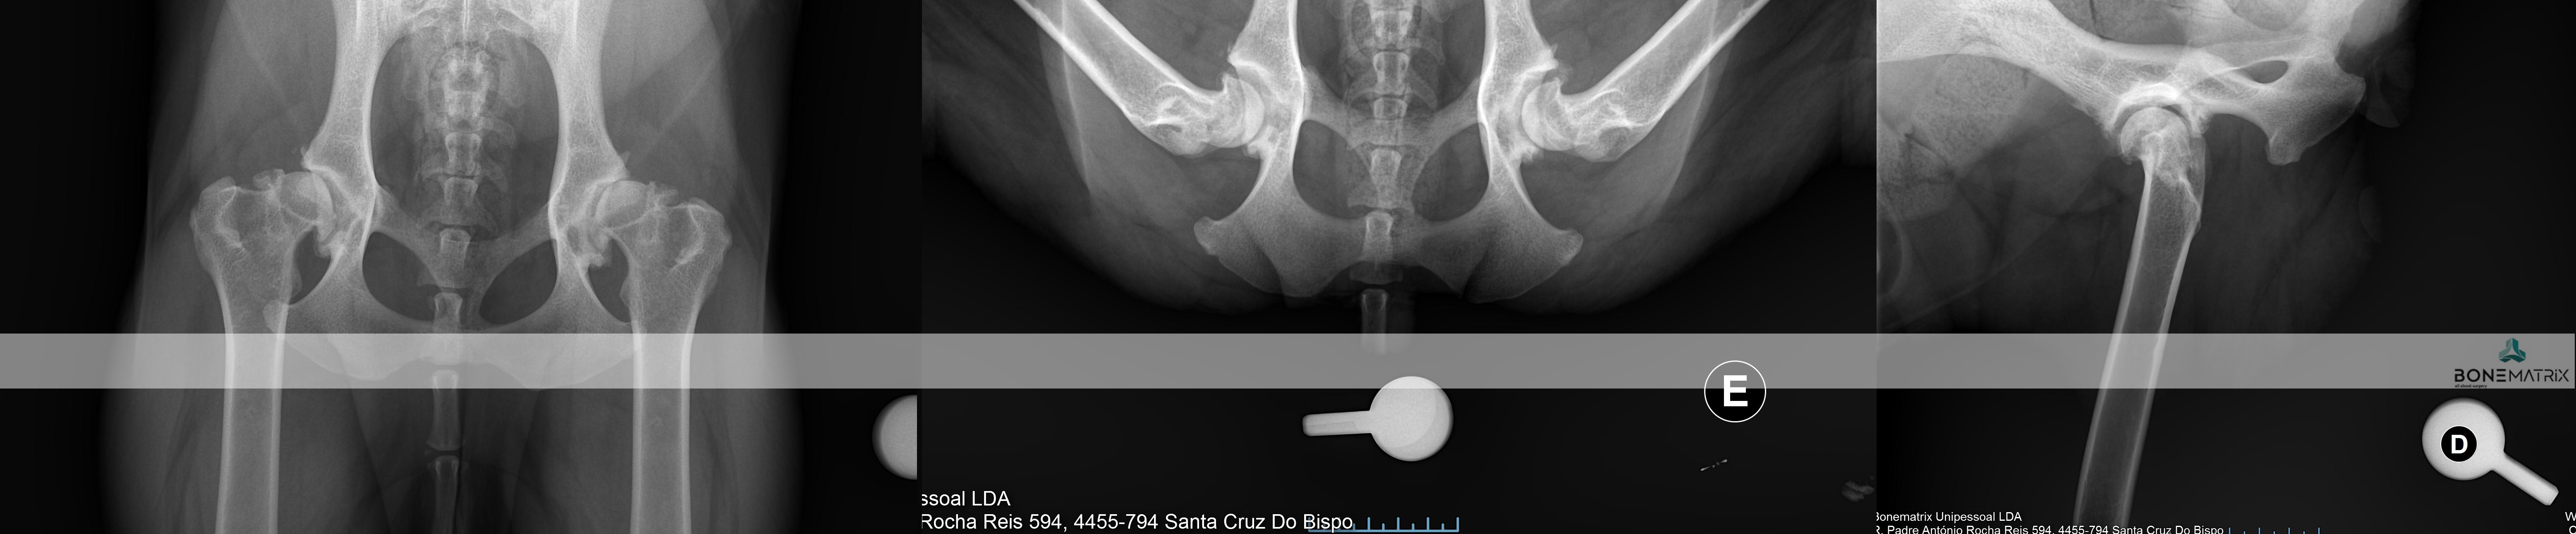

O que é?

A displasia de anca é uma patologia de desenvolvimento expressa na articulação coxo-femoral (entre o fémur e a pélvis). Esta é a doença ortopédica mais comum nos cães.

A sua origem é maioritariamente genética, podendo por vezes apresentar também uma influencia ambiental.

Como se desenvolve a doença de displasia de anca?

Inicialmente existe uma laxitude dos tecidos moles (capsula articular e musculatura envolvente) que permite juntamente com uma má cobertura da cabeça femoral pela componente óssea da pélvis (acetábulo). Estes fatores em conjunto levam à possibilidade de um movimento excessivo entre os componentes desta articulação, o que faz com que seja possível luxar cabeça femoral.

Esta luxação ocorrendo repetidamente leva ao desenvolvimento de alterações ósseas de ambas as componentes articulares que contribuem para a exacerbação da capacidade de luxação. Entrando assim num ciclo a capacidade de luxação leva a alterações articulares que permitem cada vez mais a luxação da articulação.

Esta movimentação dentro da articulação eventualmente leva ao desenvolvimento de um quadro de osteoartrite que conforme a severidade da doença se poderá apresentar também este com uma severidade correspondente.

O diagnóstico de displasia de anca deve ser realizado idealmente antes dos 5 meses, daí a importância do despiste precoce da doença.

Uma vez que este seja detetado cedo na vida do animal poderão ser consideradas opções de tratamento preventivo. Na maioria destes casos os animais apenas apresentam laxitude articular, sendo com frequência assintomáticos clinicamente. Por este motivo a intervenção cirúrgica nestas idades impede que um animal que iria desenvolver a doença a desenvolva efetivamente ou então que desenvolva apenas um quadro de osteoartrite muito ligeiro, que possa ser gerido medicamente numa idade geriátrica.

O diagnóstico é feito com recurso a um estudo radiográfico de despiste de displasia de anca (este estudo pode ser realizado a partir dos 4 meses).

O tratamento indicado depende da idade do paciente e das características estudadas da articulação.

Quando a idade do paciente o permite e este se revela um bom candidato, pode em idade imatura, ser realizada uma DPO (double pelvic osteotomy), sendo este um procedimento preventivo do desenvolvimento de displasia de anca.

Quando o animal é adulto a única opção de tratamento curativa passa pela prótese total de anca (THR). Esta permite substituir a articulação afetada na sua totalidade e devolver a qualidade de vida ao paciente até ao fim da vida dele.

DPO (double pelvic osteotomy) é um procedimento preventivo realizado em pacientes onde o despiste de displasia de anca prevê o desenvolvimento desta doença.

Inicialmente deve ser realizado um despiste de displasia de anca com recurso a um estudo radiográfico especifico para que o paciente seja avaliado e seja definido como um bom candidato à aplicação desta técnica.

A DPO consiste na realização de dois cortes ao nível da pélvis que permitem a rotação do fragmento criado. Este fragmento inclui a porção articular da pélvis, na articulação coxofemoral (o acetábulo).

Ao rodar este fragmento conseguimos uma maior cobertura da cabeça femoral pelo acetábulo, impedindo o movimento de saída da cabeça femoral de dentro do acetábulo. Ao impedir este movimento (laxitude articular) impedimos o desenvolvimento de lesões de osteoartrite provocada por ele, e desta forma impedimos o desenvolvimento da doença de displasia de anca.

Após rotação do fragmento, este é estabilizado na posição pretendida com recurso a placas bloqueadas especializadas para a realização desta cirurgia, garantindo assim a cicatrização do osso no ângulo previamente definido.

Este procedimento deve ser realizado idealmente aos 5.5 meses daí aí importância dos despiste de displasia de anca serem realizados muito cedo na vida do animal.

Os pontos essenciais que definem um bom candidato são a idade do paciente, desenvolvimento mínimo de osteoartrite a nível articular e presença de um sinal de Ortolani positivo (teste realizado durante a consulta pré-despiste).

Qual a taxa de sucesso esperada?

Após a realização desta cirurgia a claudicação irá resolver-se por norma em 3 meses após a cirurgia.

A taxa de sucesso de aplicação desta técnica é de cerca de 90% onde os paciente apresentam desde uma melhoria significativa até ao retorno à condição normal. Em alguns casos podem ser desenvolvidas alterações de osteoartrite ligeiras, mas por norma não são suficientes para provocar claudicação até que o paciente seja geriátrico.